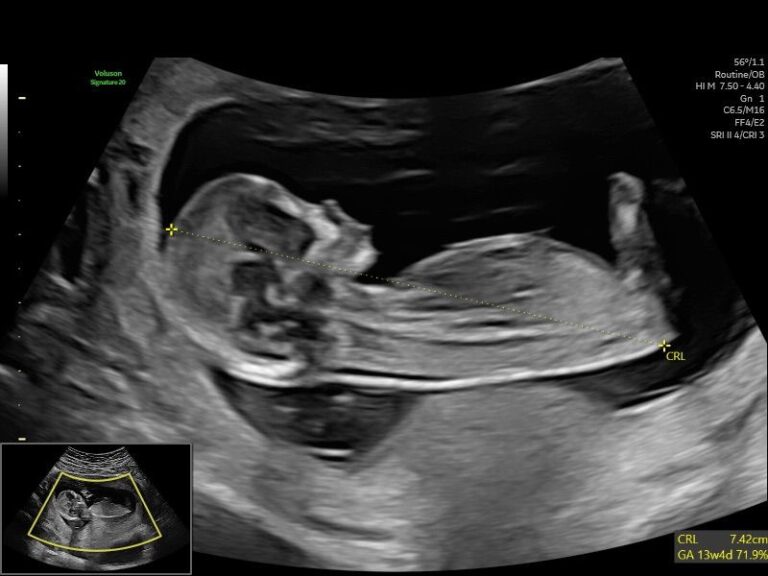

12-Week Advanced Scan+

Gestation: 12-14 Weeks

Gain valuable insights into your baby's development with our 12-Week Advanced Scan+. Performed by our skilled clinical specialist sonographers, this ultrasound helps determine gestational age and assess the nuchal fold. Looking for "ultrasound near me"? Our private ultrasound near me clinic provides a comfortable and supportive environment for this important scan.